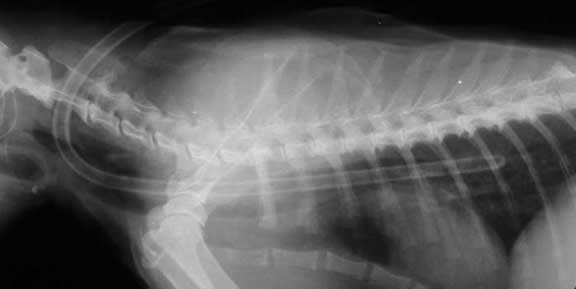

Cat’s have clavicles that are just remnants of the original